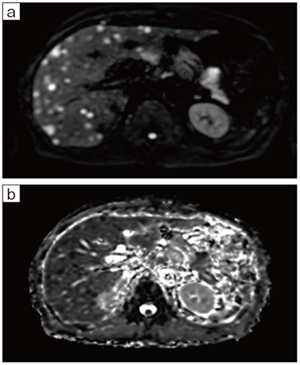

ECHELON Smart ZeroHeliumでは,頭部・腹部を中心に月に約150件の検査を実施している。MRI検査を担当する川邊技師は,「更新前と検査数は変わりませんが,新たに全身body DWIを開始してスクリーニングなどに活用しているほか,以前は造影で行っていた下肢MRAを非造影で行えるようになりました」と説明する。下肢MRAは糖尿病の合併症である末梢血管の狭窄の評価で撮像するが,非造影撮像が可能になったことで,糖尿病が進行し腎機能が低下している患者も検査可能になると期待している。

陣内理事長は画質の向上が診療に与える影響について,「長寿化により糖尿病の患者さんを長期にわたり診療していると,がんも増加します。ECHELON Smart ZeroHeliumでは,MRCPの画質が大きく向上したと感じており,症状が現れにくい肝胆膵がんの早期診断の撮像に活用しています。前立腺がんもクリアな画像によりある程度の判断が可能と考えており,PSA値と総合的に判断して適切に紹介できるようになったと思います」と話す。